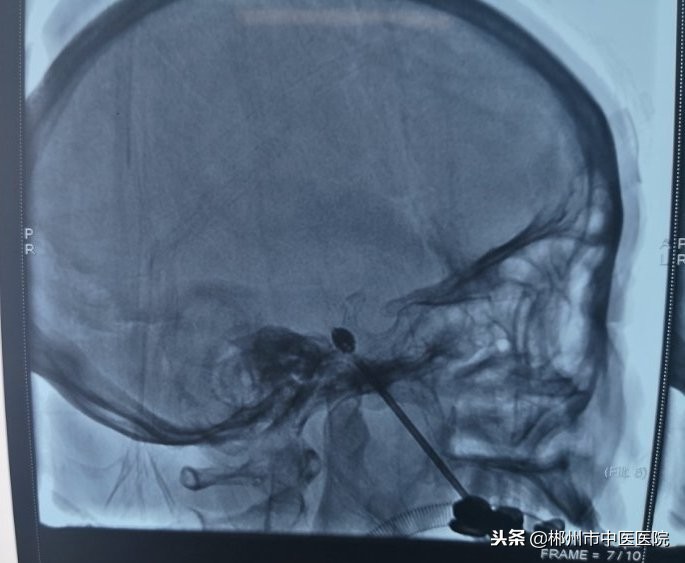

针尖抵达颅底卵圆孔,造影剂充盈球囊

手术当天,经周密术前准备,治疗开始。在麻醉科医护人员的配合下,李孝生主任从患侧口角旁经过皮肤插入穿刺针,在DSA监视下,通过鞘管将一个微球囊导入卵圆孔处三叉神经的半月节,然后缓慢注入对比造影剂充盈球囊,再通过扩张的微球囊将神经纤维压迫,从而阻断三叉神经感觉根传导功能,以达到解除三叉神经痛的效果。